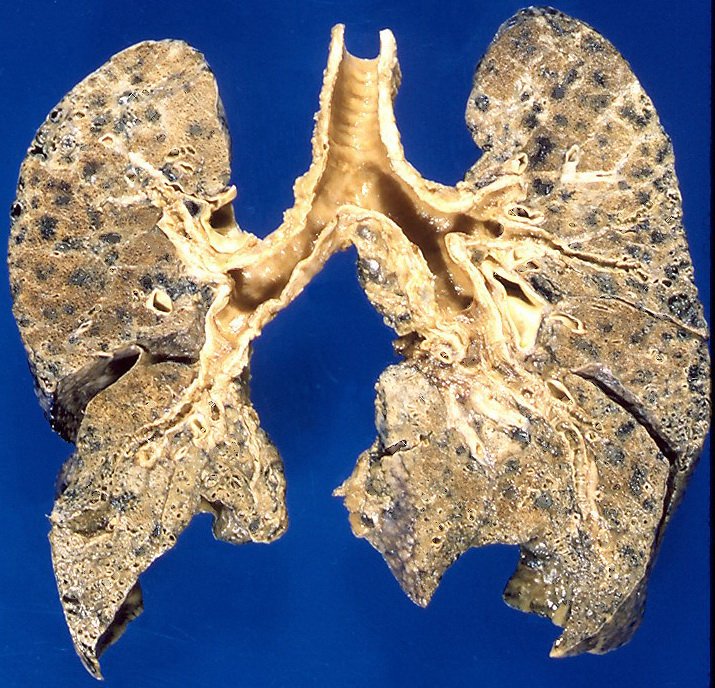

Día Mundial de la Enfermedad Pulmonar Obstructiva Crónica

La Enfermedad Pulmonar Obstructiva Crónica (EPOC, o COPD por sus siglas en inglés) es una de las enfermedades crónicas más …